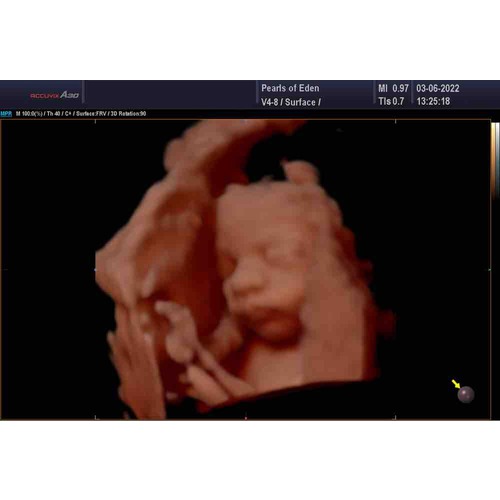

Eerste zwangerschap 3D echo gedaan met 28 weken en placenta lag ook voor. Prima beeld gehad en ons zoontje goed kunnen zien. Paar keer moeten porren en springen zodat meneer toen zou mee werken. Deze keer weer 3D echo gepland met 28 weken om ons dochtertje te kunnen zien. Placenta ligt nu achter